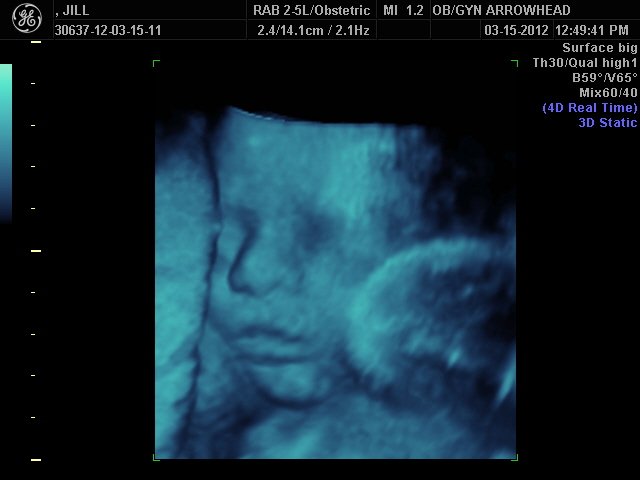

We offer complimentary 3D/4D Ultrasounds to all our OB patients around 30 weeks! The following photos are some examples of our work, shown with permission from our patients.